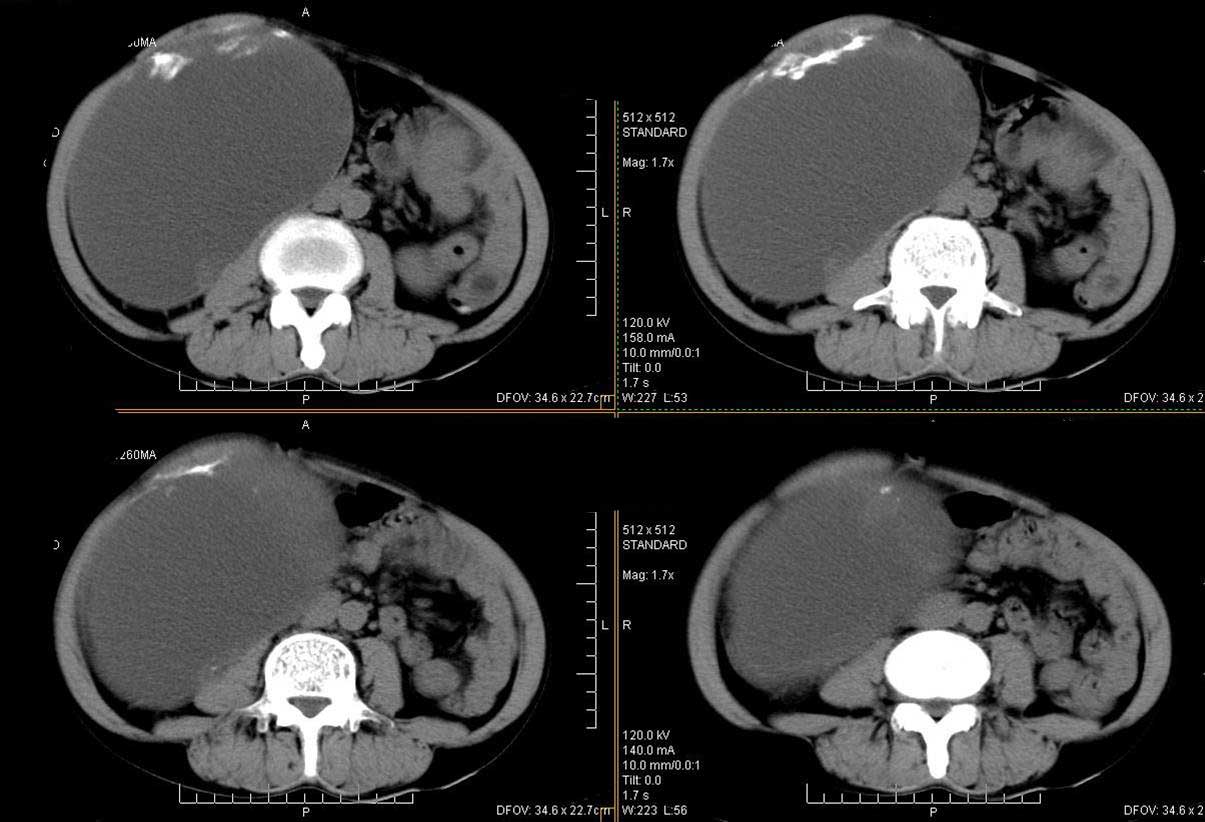

右肾脏巨大囊样影、囊壁有钙化,囊样影轻度强化有软组织成份。不除外畸胎瘤可能。

巨大囊性肿块,囊壁较厚有强化,有团片状钙化,病灶内下方灶内见片絮状高密度影,增强有轻中度强化,考虑囊性肾癌可能性大

右肾上部巨大的囊实性影,实性部分轻度强化。壁有钙化。考虑右肾囊腺癌。右肾盂积水。

定位;肾明显与病灶杯口相交,可以肯定病变来自右肾。

定性;病灶囊性为主,前下部含实性成分,及钙化,部分壁厚薄不均。

肾囊实性病变有;1,囊性肾癌2,囊性肾瘤。3,复杂囊肿。4,重复肾伴积水。然2、3壁相对规则。

综上考虑;囊性肾癌》重复肾伴积水。

可考虑 1畸胎瘤 2肾包囊虫 3囊性肾瘤或囊性肾癌 4重复肾伴积水。